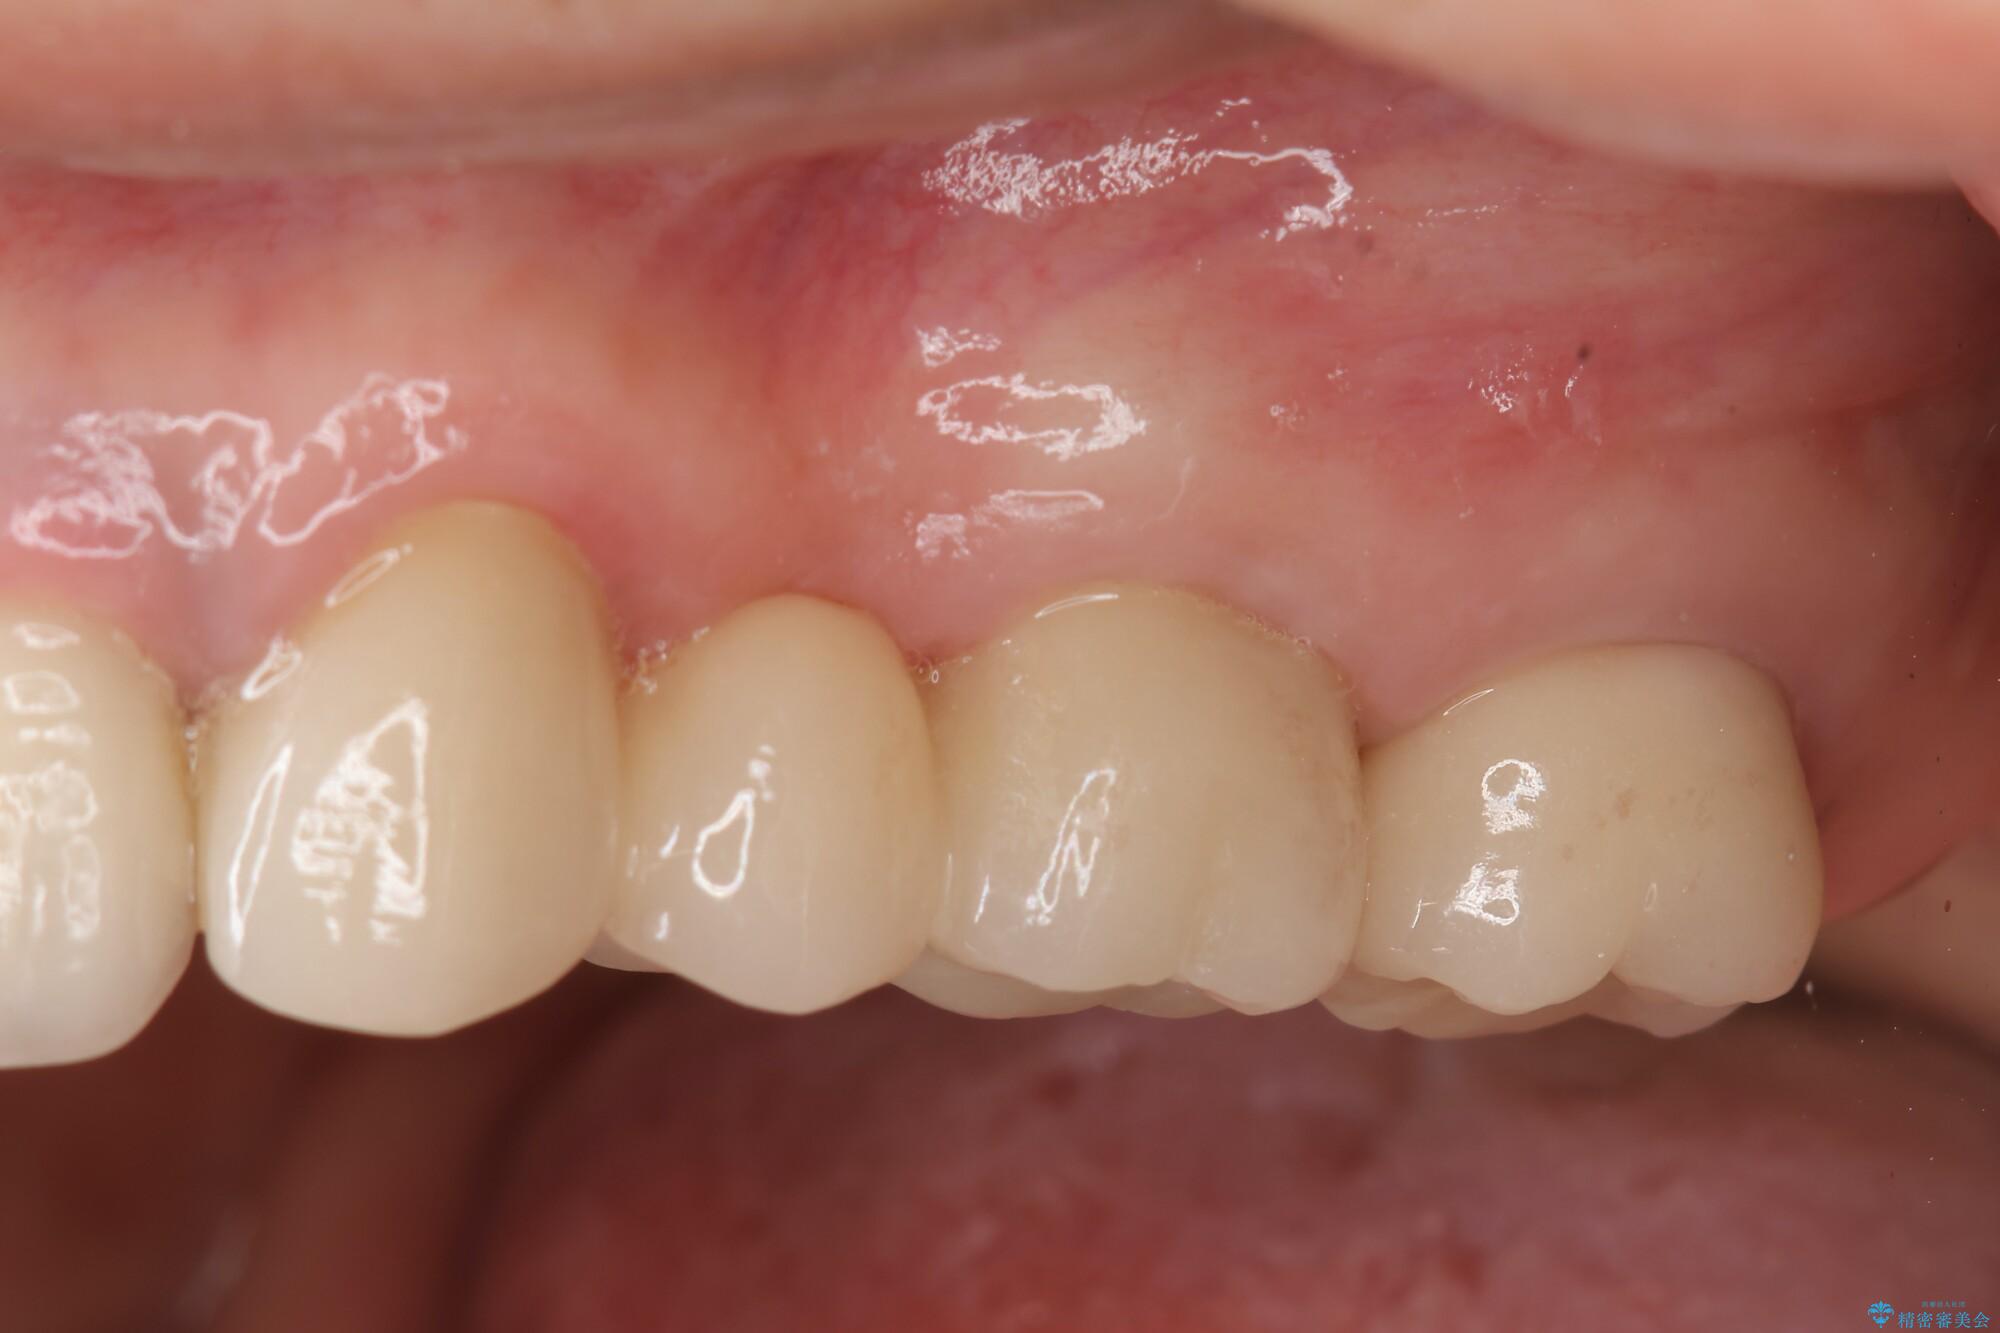

治療後について

ブリッジに審美的でないイメージやあまり良くないイメージをお持ちの方を多々お見受けしますが、適切な設計とすることで、見た目に自然で審美的なブリッジ治療を行うことができます。